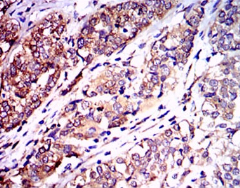

IHC    1/200 - 1/1000